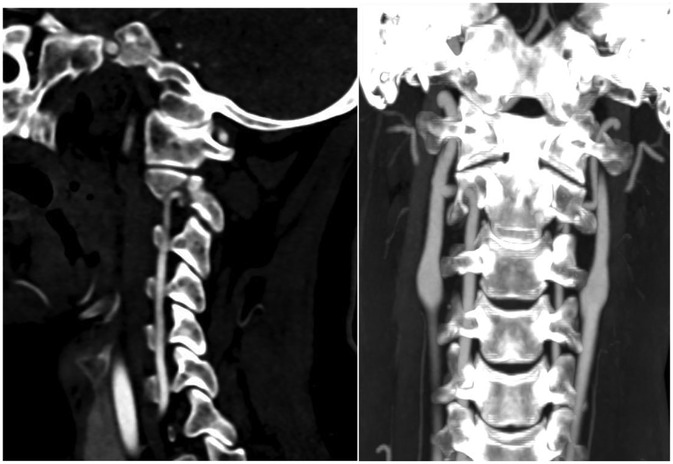

Objective: This retrospective study aimed to analyze the accuracy and safety of pedicle screw placement in upper cervical spine surgery for Hangman's fractures, particularly in cases with high-riding vertebral artery (HRVA) at C2, using navigation technology and 3D-printed patient-specific templates. Methods: We included 33 patients with Hangman's fractures who underwent posterior cervical fixation with bone graft fusion or non-bone graft fusion surgery between January 2013 and January 2023. Patients were divided into two groups based on the intraoperative pedicle screw placement method: Group A (n=15) utilized a navigation system, and Group B (n=18) used a 3D printed navigation template. Clinical and radiological data were collected and compared. Results: One hundred and forty-four screws (66 navigated, 78 3D-printed templates) were inserted without vertebral artery, spinal cord, or nerve injury. Operative time per screw: Group A 24.0±5.6 min vs Group B 18.7±4.1 min; mean difference 5.3 min (22% reduction; 95% CI -9.1 to -1.5; P=0.018). Intra-operative blood loss:152±29 mL vs 105±19 mL; mean difference 47 mL (95% CI -66 to -19; P=0.001). Overall accuracy (Grade 0+1) was 98.5% (65/66) vs 98.7% (77/78) (odds ratio 1.05; 95% CI 0.11-10.2; P=0.97). In the Type-III fracture subgroup (8 screws per group), templates achieved 100% accuracy vs 87.5% with navigation (P=0.032) and lower cortical penetration (12.5% vs 37.5%; P=0.008). Post-operative VAS and NDI improved comparably (all inter-group P>0.05). At 24-month follow-up, all fractures had healed; C2/3 fusion rates did not differ (facet fusion 100% vs 100%; inter-body fusion 39% vs 39%; P>0.99). Conclusion: The use of 3D-printed patient-specific templates in upper cervical spine surgery for Hangman's fractures, especially in the presence of HRVA, is effective and safe. It offers comparable accuracy to navigation-assisted surgery while reducing operative time and blood loss. This approach may be particularly beneficial in minimizing the risk of vertebral artery injury and optimizing surgical outcomes. Compared to navigation technology, it can effectively improve the accuracy of screw placement in extremely unstable fractures.